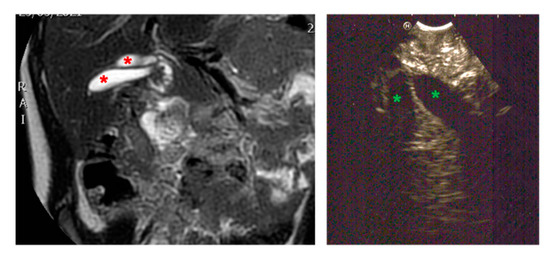

3.2.1. Congenital Malformations (Duplication Cysts)

3.2.2. Biliary Tree Abnormalities

3.2.3. Proliferative Disorders

| Radiological investigations | MR, US, EUS, X-ray | US, MR, CT-scan, barium swallow | US, MRI | |

| Endoscopic instrumentation | EBUS | EBUS | EG-3870UTK Linear-Array Ultrasound Gastroscope | |

| Management | MIS (laparoscopic resection of gastric duplication cysts) | MIS (thoracoscopic resection of esophageal duplication cyst) | Planned endoscopic removal by unroofing and mucosectomy | |

| Endoscopic Advantages/Limitations | Reduction in the diagnostic possibilities by identification of cysts surrounded by gastrointestinal wall layers | Definition of the relationships with surrounding tissues | Anatomical definition of surrounding structures (in particular, the biliary tree and pancreatic duct) | |

| Symptoms | Acute pancreatitis, pain in right hypochondrium | Icterus, pancreatitis | Chronic pancreatitis with choletithiasis, genetic-based | No |

| Diagnosis (prenatal evaluation yes/no) | Cholelithiasis and choledocholithiasis in duodenal atresia (duodeno-jejuno anastomosis at birth) and pancreas divisum (yes) | Choledochal cyst (Todani I) and choledocholitiasis (no) | Mutation of the gene PRSS1, Cholelitiasis, pancreatic duct duplication (no) | Gallbladder duplication Annular pancreas Duodenal duplication (yes) |

| Radiological investigations | US, MR, CT Scan, VR HMD | US, Cholangio MR | US, X-ray, Cholangio MR, CT, VR HMD | US, Cholangio MR, CT |

| Endoscopic instrumentation | EG-3870UTK Linear-Array Ultrasound Gastroscope | EBUS + Duodenoscope | Duodenoscope, EG-3870UTK Linear-Array Ultrasound Gastroscope | EBUS |

| Management | MIS (laparoscopic cholecisectomy) with LCBDE | 1. ERCP + sphincterotomy + stone removal 2. Open surgery: choledochal cyst removal and Roux-en-Y bilio-digestive anastomosis | 1. EUS + ERCP + stent placement + sphincterotomy + DASE; MIS (laparoscopic cholecystectomy) with LCBDE 2. ERCP and pancreatic stent replacement | MIS (laparoscopic cholecystectomies) with attempted LCBDE (failure for fibrosis) |

| Endoscopic Advantages/Limitations | Anatomical definition ERCP technically impossible for difficulties in reaching the papilla | Diagnostic and therapeutic procedures | Effective biliopancreatic drainage permitted postponed cholecystectomy and pancreatic preservation | Anatomical definition |